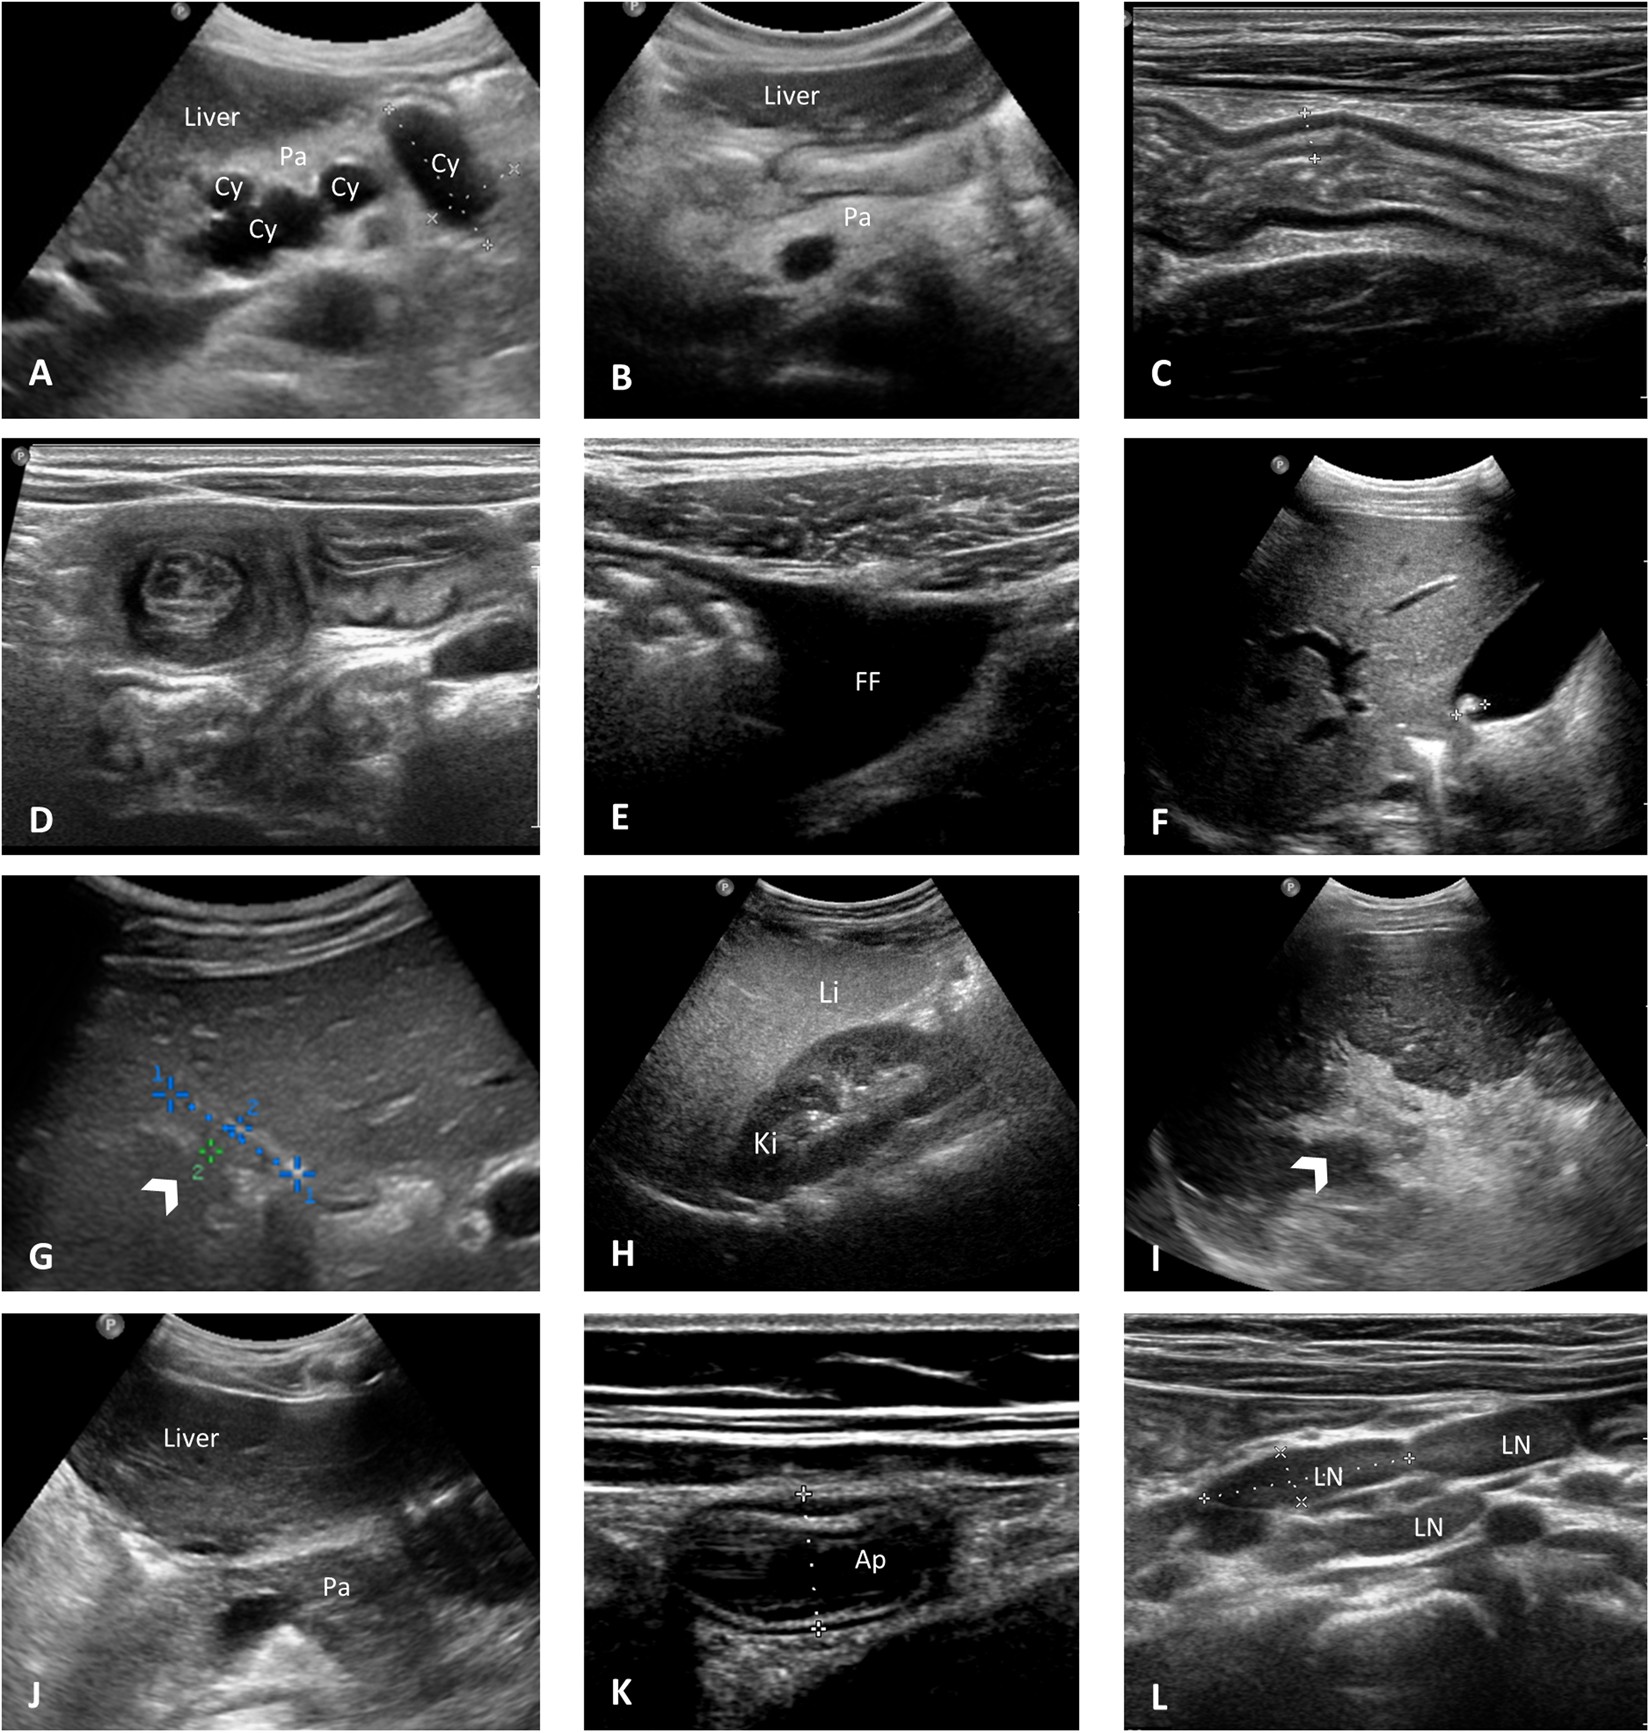

Figure 2

Specific US abnormalities identified in the Jena University CF cohort. (A) Pancreatic cystosis in an asymptomatic 41-year-old female patient heterozygous for G551D showing a hyperechoic pancreas (Pa) containing multiple cysts (Cy) with sizes approximately of 21 × 34 × 20 mm and 21 × 40 × 24 mm. CFAbd-Score: 82 (*range: highest burden of symptoms [0 points] to no symptoms [100 points], respectively). (B) Hyperechoic pancreas (Pa) with fat replacement as typical for pancreatic lipomatosis in a 10-year-old female patient homozygous for F508del with pancreatic insufficiency (symptom score: 95). (C) Longitudinal US image of the bowel wall in the terminal ileum measuring approximately 5 mm in a context of thickened bowel wall in a 19-year-old patient homozygous for F508del (symptom score: 81). (D) Transversal section of the small bowel showing the classic target sign appearance of intussusception in a 3-year-old female asymptomatic patient homozygous for F508del (symptom score: 96). (E) Free fluid (FF) in the right lower quadrant in a 32-year-old male patient homozygous for F508del with severe liver disease (symptom score: 80). (F) Single gallstone in a 12-year-old male asymptomatic patient heterozygous for G551D (symptom score: 100). (G) Gallbladder (arrow) in a 11-year-old female patient heterozygous for G551D measuring 18 × 4 mm in a context of micro-gallbladder (symptom score: 88). (H) US image of liver steatosis in a 4-year-old male patient homozygous for F508del, showing diffused increased echogenicity of the right lobe of the liver (Li) relative to right kidney cortex (Ki) (symptom score: 85). I) Severe periportal fibrosis (arrow) in a 28-year-old male patient heterozygous for F508del/R347P with cystic fibrosis liver disease (CFLD) (symptom score: 87). (J) Isoechoic pancreas (Pa) relative to liver in a 18 year-old female patient heterozygous for G551D with pancreatic sufficiency (PS) in longitudinal sonogram at level of the pancreatic head (symptom score: 99). (K) US scan of the appendix (Ap) in a 10-year-old asymptomatic female patient homozygous for F508del. Note the thickened aspect of the appendix (diameter of 9 mm) (symptom score: 95). (L) Enlarged mesenteric lymph nodes (LN) greater than 18 mm in the larger axis in a 10-year-old asymptomatic patient homozygous for F508del, in a context of an inflammatory etiology (symptom score: 95).